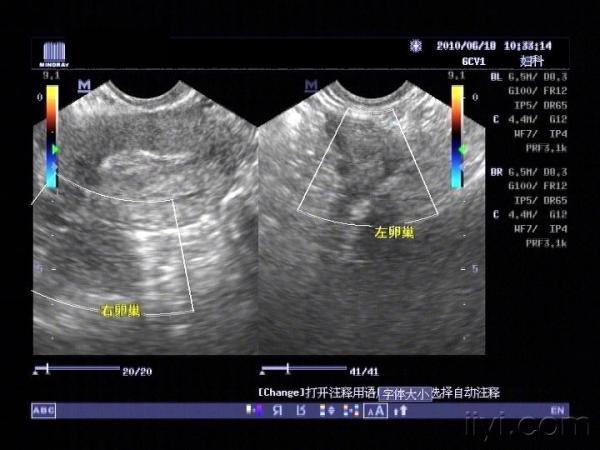

双侧卵巢

右侧附件区和左侧附件区各见一囊性包块

在双侧卵巢清晰显示的情况下,附件区囊状光团,尤其是呈肠管形时,输卵管积液可能极大。